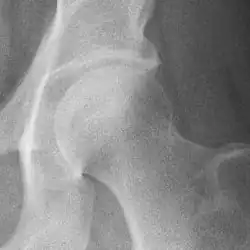

Hip

Hip joint with no signs of osteoarthritis.

The most commonly used radiographic classification system for osteoarthritis of the hip joint is the Kellgren–Lawrence system (or KL system).[6] It uses plain radiographs.

Osteoarthritis of the hip joint may also be graded by Tönnis classification. There is no consensus whether it is more or less reliable than the Kellgren-Lawrence system.[8]

Severe (Tönnis grade 3) osteoarthritis of the hip.